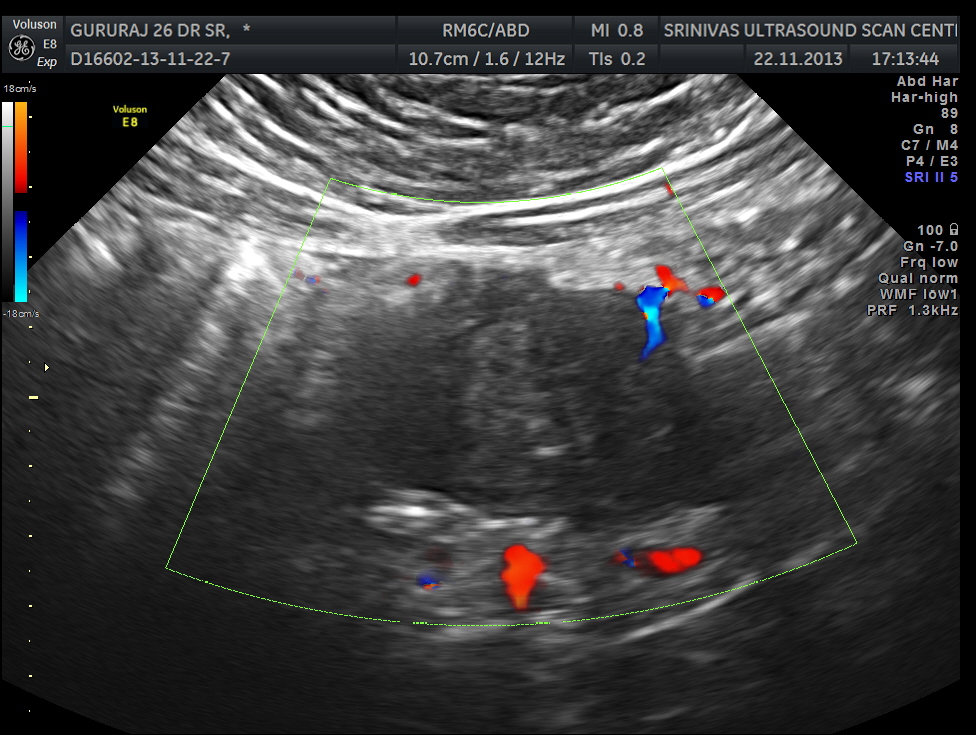

The following image was obtained with the transducer in the mid epigastric region and an inch to the left of the mid line.

This mass visualised there . This was antero-lateral to the aorta and showed mixed echotexture , with some vascularity.

This was not mobile and all i could offer was a description of what was seen with the impression of a mass of unknown origin – ?? enlarged node and advised further work up.